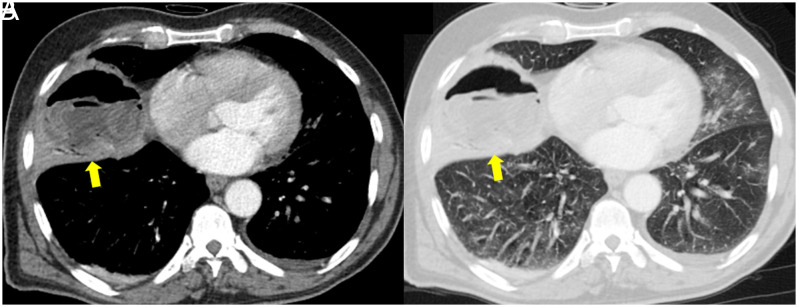

Abstract Image